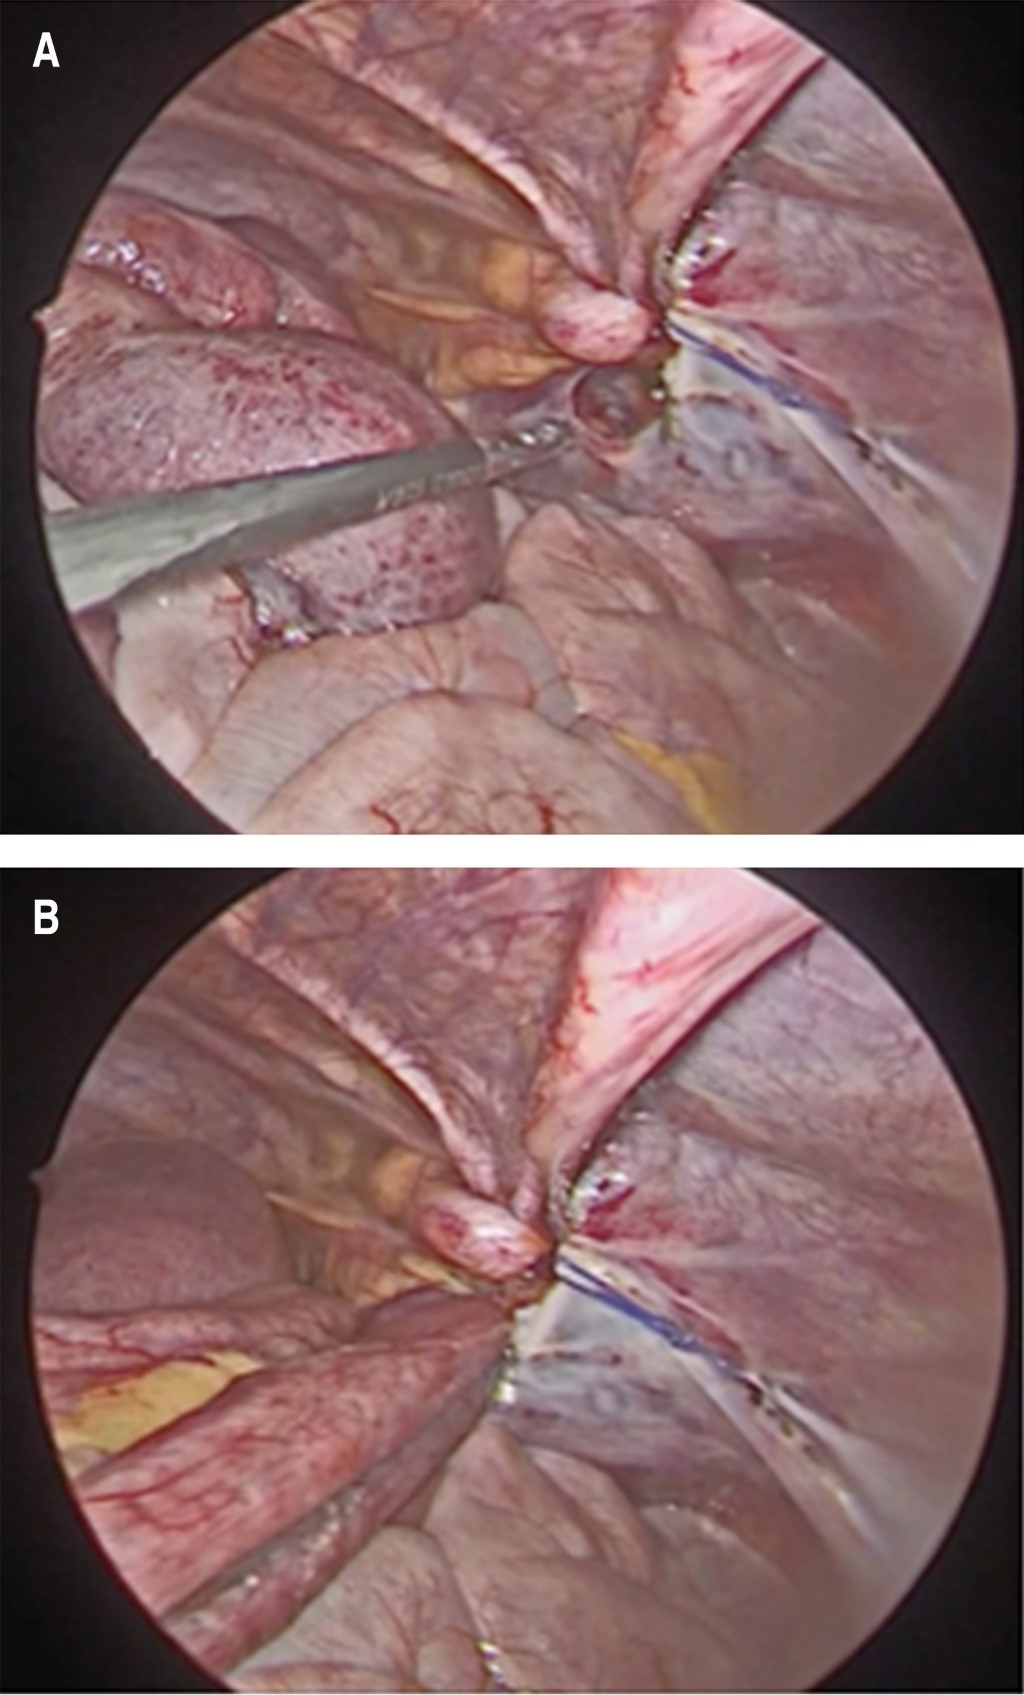

Se ingresó paciente para observación, hidratación por vía intravenosa con solución Ringer lactato y manejo médico sintomático persistiendo con sintomatología, por lo cual se indicó colocación de una sonda nasogástrica (SNG) y una tomografía computarizada (TC) de abdomen con contraste intravenoso. La TC de abdomen demostró obstrucción de intestino delgado con sospecha de hernia interna (Figura 1). Basado en hallazgos clínicos y radiológicos, se decidió realizar una laparoscopia diagnóstica de emergencia. Se identificó como origen de la obstrucción un asa de intestino delgado herniada en el espacio preperitoneal a través de un defecto peritoneal (Figura 2). No se identificaron datos de sufrimiento de asa, por lo cual se redujo la hernia y posterior cierre del defecto del peritoneo con poliglactina 910 2-0 puntos cruzados.

Figura 2